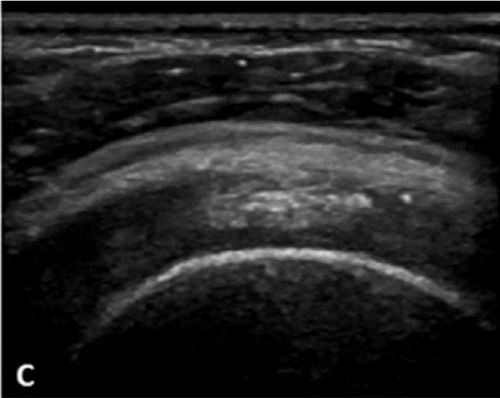

Υπερηχογραφική απεικόνιση της ασβεστοποίησης του ώμου (Farin)

Στην κλινική πράξη είναι αυτή που δίνει τις πιο αξιόπιστες πληροφορίες για τη σύσταση της ασβέστωσης.

| Τύπου Α: Υπερηχογενής με έντονη ακουστική σκιά | Τύπου Β: Υπερηχογενής με ήπια ακουστική σκιά | Τύπου C: Υπερηχογενής χωρίς ακουστική σκιά |

Με βάση αυτή την ταξινόμηση μπορούμε να εκτιμήσουμε την αποτελεσματικότητα μιας θεραπείας Barbotage

Με λίγα λόγια, όταν η ασβέστωση είναι μαλακής ή μέτριας σκληρότητας, το αποτέλεσμα της θεραπείας Barbotage προβλέπεται άριστο/πολύ καλό ενώ αν είναι σκληρής σύστασης τότε το αποτέλεσμα θα είναι μέτριο/φτωχό

(καλύτερη ένδειξη για barbotage: ασβέστωση Farin B και C , Gartner/Hayer II,III)